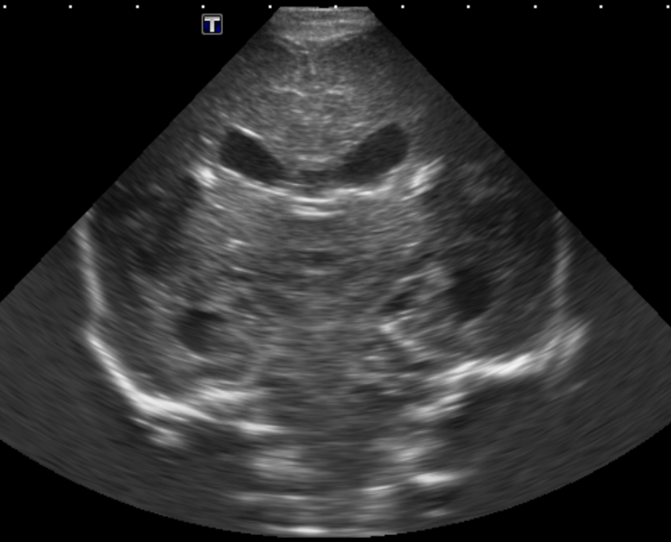

CSF spaces/ventricular system

There is a prominence of the extra axial fluid spaces. [Yes/No]

There are debris/septations in the extra axial fluid spaces. [Yes/No]

There are debris/septations in the ventricles. [Yes/No]

There is a subdural collection on the right/left side. [Yes/No]

There is prominence of the ventricular system. [Yes/No]

There is an asymmetry of the ventricular system. [Yes/No]

There is a cavum septum pellucidum. [Yes/No]

There is a midline shift towards right/left. [Yes/No]

The choroid plexus is bulky/lobulated. [Yes/No]

There is a choroid plexus cyst measuring… [Yes/No]

There are debris/clots in the occipital horn. [Yes/No]

There is a posterior fossa cyst measuring… [Yes/No]

The tentorium is elevated/depressed. [Yes/No]

The lateral ventricle/s are dilated. [Yes/No]

The third ventricle is dilated. [Yes/No]

The 4th ventricle is dilated. [Yes/No]

There are pseudo cysts. [Yes/No]